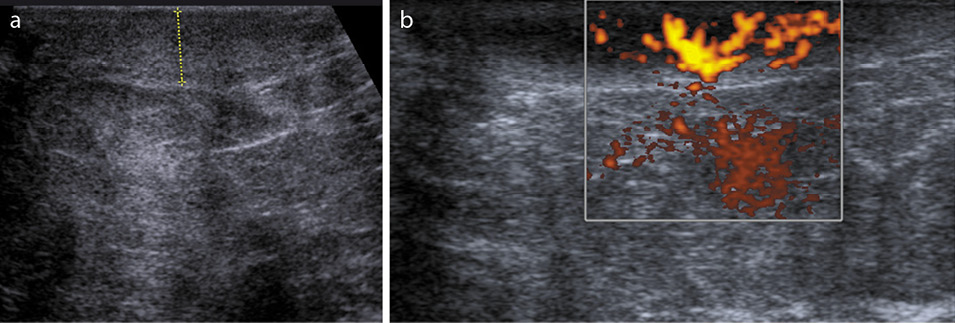

Среди всех методов визуализации в диагностике локального и диффузного отека кожи маммография характеризуется наиболее высокой эффективностью за счет возможности анализа симметричных зон «суммационного» изображения органа. При этом основным признаком отека кожи является ее утолщение (рис. 1). С помощью ультразвукового исследования молочных желез также возможно визуализировать отек кожи за счет утолщения и активного кровоснабжения кожного покрова (рис. 2). Но данный метод субъективен и обладает низкой результативностью в выявлении локального отека кожи. Роль магнитно-резонансной томографии молочных желез в решении этого вопроса незначительна (рис. 3), и поэтому этот вид визуализации не может использоваться для дифференциальной диагностики злокачественной и доброкачественной природы отека (уровень доказательности 1b, уровень рекомендаций A) [4].

Рис. 2. Сонограмма. Визуализируются утолщение кожи и активный кровоток в толще кожи.